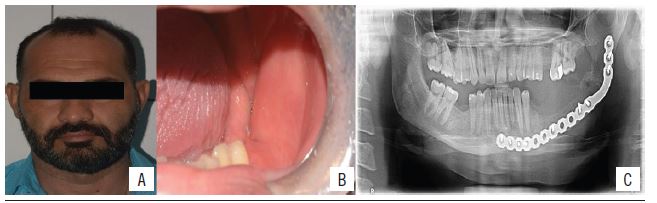

The surgical specimen was sent to the laboratory of Anatomic Pathology, and the microscopic analysis confirmed the diagnosis, as well as the disease-free margins. In the immediate postoperative period, the patient had no pain, but edema compatible with the performed procedure and limited oral opening. Active mechanotherapy with rubber bands was used since the first day after surgery, both for temporary maxillomandibular fixation and for immediate physiotherapy. The present case has been followed up for six months (Figure 4).